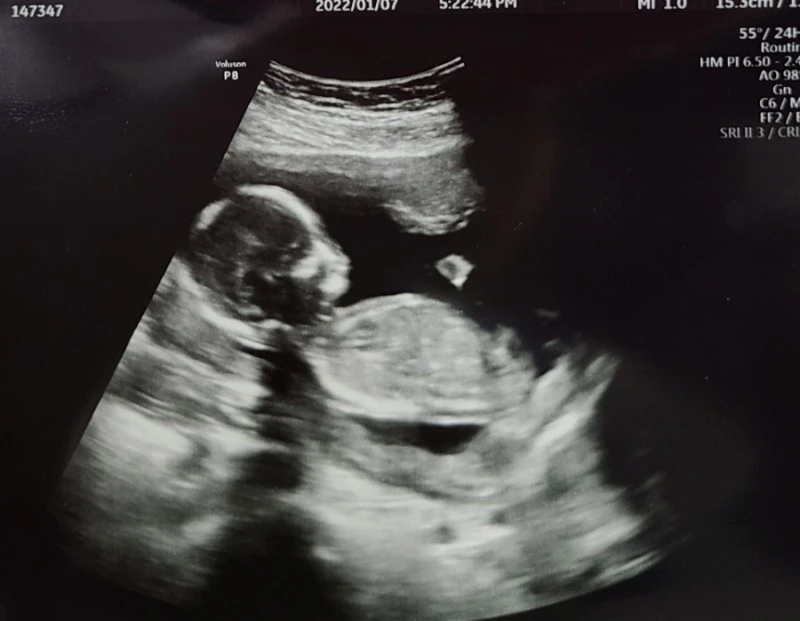

2021년 10월 30일 첫 초음파 확인

2021년 11월 6일 우렁찬 심장박동 수 확인

2년 넘게 이어졌던 지난했던 인공수정과 시험관 시술, 결혼 후 6년 동안 겪은 5번의 임신과 5번의 유산 후 비자발적 딩크족의 삶을 원했던 엄마와 자녀 입양을 원했던 아빠는 2021년 가을 기적처럼 새 생명이라는 선물을 받게 되었어.

참, 너의 태명이 왜 딱풀이 이었는지 아니? 딱풀처럼 떨어지지 않고 끝까지 잘 붙어있다 만나길 바라며 붙인 태명이야.